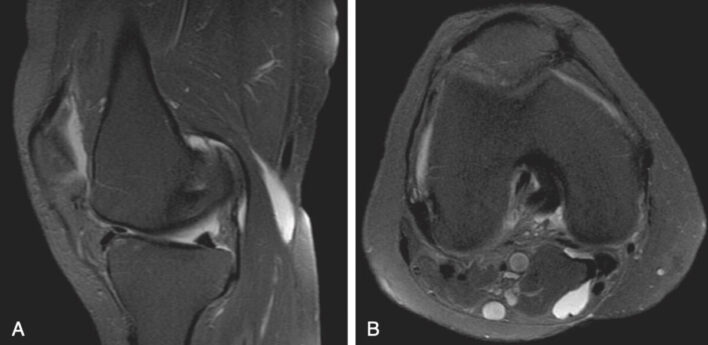

- Chụp MRI hiển thị giải phẫu của toàn bộ khớp và là một thăm dò nhạy để xác định nang Baker cũng như nguyên nhân có thể có. Chụp cộng hưởng từ cũng giúp loại trừ các khối u và xác định các thay đổi bệnh lý để có thể phẫu thuật cắt bỏ. Trên phim MRI, nang Baker xuất hiện dưới dạng các khối có giới hạn rõ với cường độ tín hiệu thấp trên ảnh T1W và cường độ tín hiệu cao trên ảnh T2W (Hình 3).